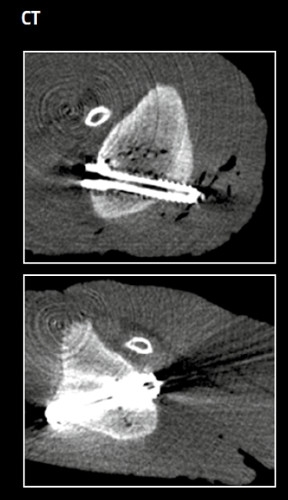

The histological images show the phases of the transformation process of a MAGNEZIX® CS in rabbit animal models. The image shows a cross-section of the hollow compression screw at various post-operative times.